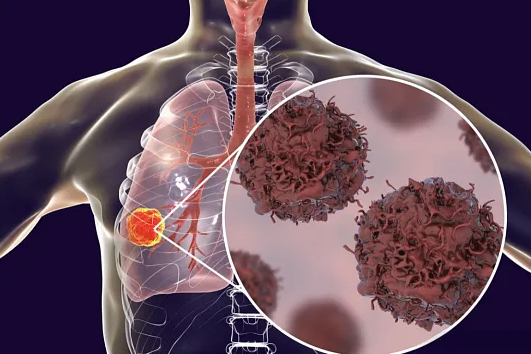

肺癌:发病率最高,小细胞癌最凶险

肺癌是国内发病率最高的癌症,不同类型复发风险差很多。小细胞肺癌长得快、转移早,很多患者术后半年到一年就复发;肺腺癌里有微乳头成分的,还有术后病理提示脉管有癌栓、胸膜侵犯、淋巴结转移的,复发风险也明显升高。

术后别只拍胸片,一定要做低剂量螺旋 CT,看得更清楚。还要根据病理分期和基因检测结果,该做辅助化疗、靶向或免疫治疗的,一定要坚持做完,别因为怕副作用就放弃。